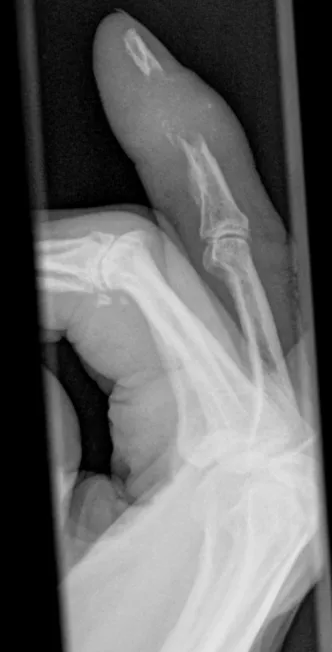

This collection contains 1 radiology images related to metastasis, including various imaging modalities such as X-rays, MRIs, CT scans, and ultrasound images commonly used in medical diagnosis and education.